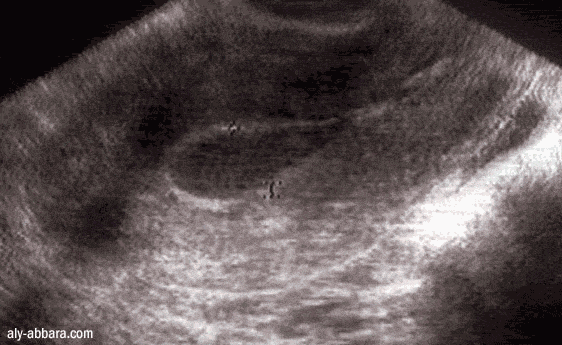

Source image : aly-abbara.com Cette image est un résultat de recherche de Google Image. Elle est peut-être réduite par rapport à l'originale et/ou protégée par des droits d'auteur. |

Saignement génital survenant en dehors des règles. On peut avoir des métrorragies après la ménopause ou à cause d'une grossesse extra utérine rompue. Dans ce dernier cas le fœtus peut s'être développé dans les trompes (au lieu de l'utérus) et ainsi, rompre un vaisseau sanguin. La métrorragie peut ainsi signer un hémopéritoine. C'est une urgence médicale. Le terme métrorragie ne préjuge en rien de l'abondance du saignement. Il ne faut pas confondre métrorragie avec ménorragie, qui définit des règles anormalement longues et abondantes.